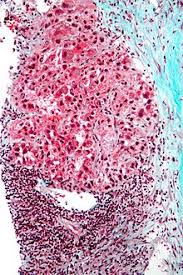

Signs And Symptoms Of Liver Cancer In Humans : Cancer Signs And Symptoms Wikipedia / Understand the main symptoms of liver cancer and when and where to get medical help.. Other terms used are malignant tumours and neoplasms. Understand the main symptoms of liver cancer and when and where to get medical help. Symptoms and signs of liver cancer (hepatocellular carcinoma) include jaundice, abdominal swelling and pain, and swollen feet. Symptoms of liver cancer include pain in the abdomen, a lump or mass under the ribs, jaundice and weight loss. When these flies bite humans, they pass on the plague.

Symptoms of liver cancer include pain in the abdomen, a lump or mass under the ribs, jaundice and weight loss. Symptoms of liver cancer can include abdominal and shoulder blade pain, jaundice, and weight loss. Signs and symptoms of gastrointestinal tract. In the united states, doctors usually discover signs of liver cancer when screening people for an underlying liver condition, such as chronic hepatitis. One defining feature of cancer is the rapid creation of abnormal cells that grow beyond their usual boundaries, and which can then invade adjoining parts of.

Most symptoms of liver cancer are not specific such as fatigue, decreased appetite and weight loss.